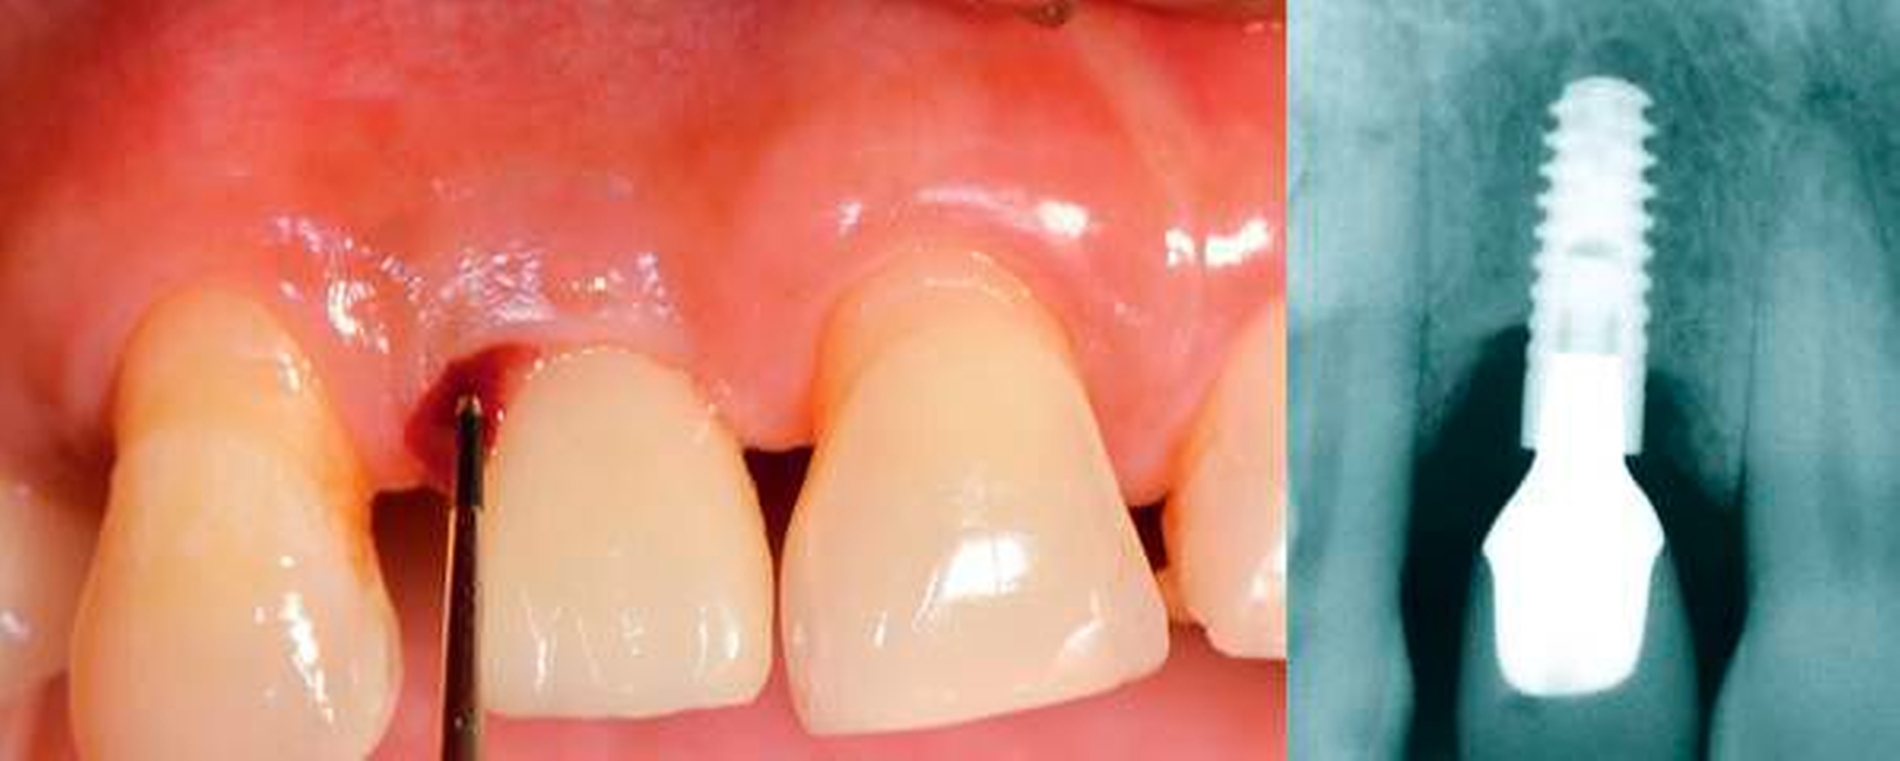

Peri-implantäre Mukositis

Die peri-implantäre Mukositis ist gekennzeichnet durch eine entzündliche Läsion in den Weichgeweben, die ein Implantat umgeben – in Abwesenheit von peri-implantärem Knochenabbau. Die Läsion befindet sich lateral zum Saum-/Taschenepithel, erstreckt sich aber nicht in die suprakrestale Bindegewebszone „apikal“ des Saum-/Taschenepithels.

Das wichtigste klinische Merkmal der peri-implantären Mukositis ist die Blutung auf sanfte Sondierung, während andere klinische Anzeichen einer Entzündung – wie beispielsweise Rötung und Schwellung – zusätzlich auftreten können. Eine Erhöhung der Sondierungstiefe ist bei einer peri-implantären Mukositis aufgrund von Schwellung oder Abnahme des Sondierungswiderstands häufig zu beobachten. Es gibt starke Evidenz dafür, dass Plaque der ätiologische Faktor bei der peri-implantären Mukositis ist. Es gibt auch Beweise dafür, dass peri-implantäre Mukositisläsionen nach der Wiederaufnahme von Maßnahmen zur Plaquekontrolle verschwinden können.

Falldefinition der peri-implantären Mukositis in der täglichen klinischen Praxis:

- Blutung und/oder Eiterung bei sanfter Sondierung

- Kein Knochenabbau